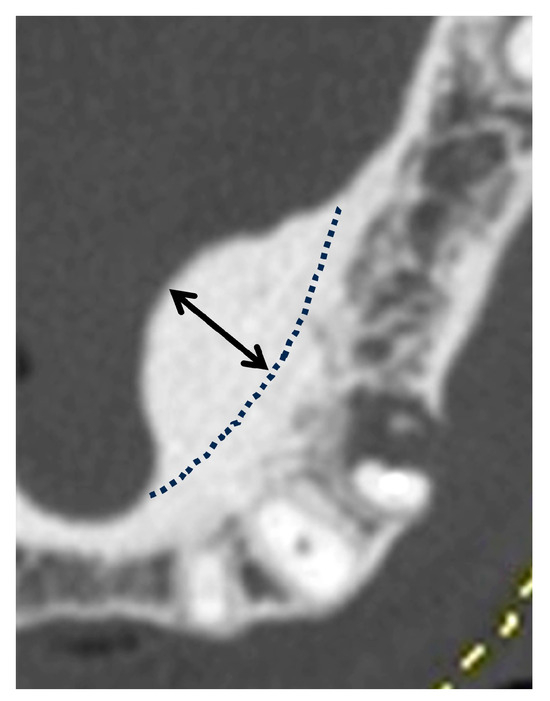

2.2. Classification of Morphology and Size

2.3. Bone Density Assessment